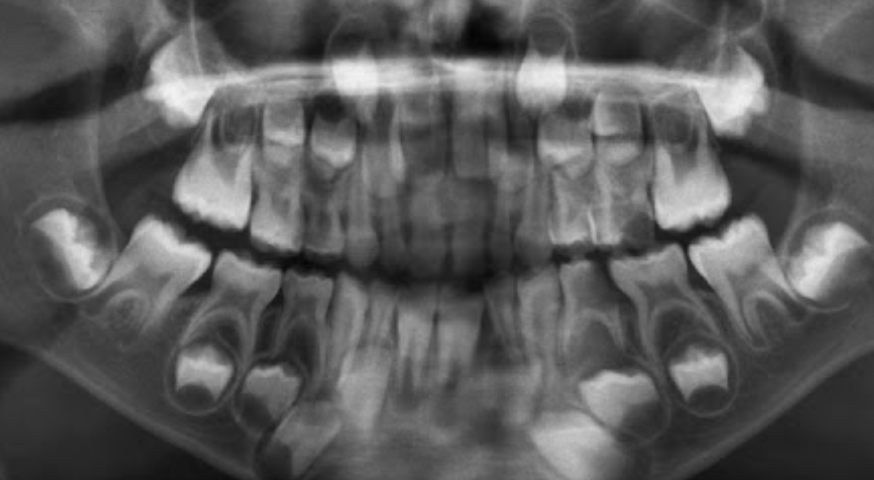

1.Ad. LOWER central incisors present? Yes. definitely 6-7 or older

1. Ad. UPPER CI present? Yes def. 7-8 y.o

3.Ad. Upper LAT incisor present (baby sheds 7-8)? NO so still under 7-8

Conc: pt is under 7